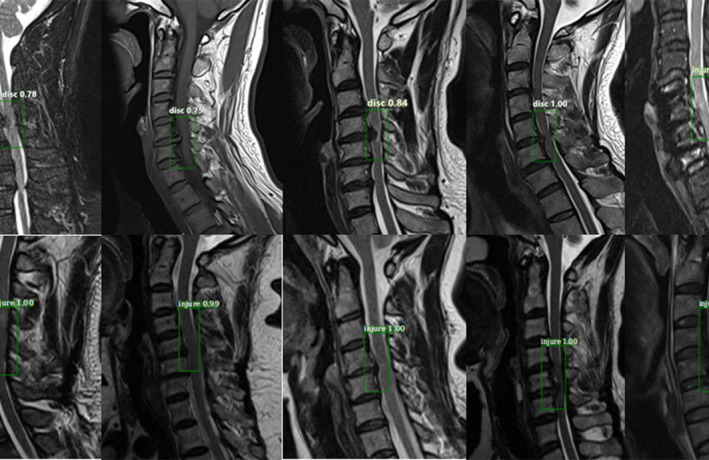

The dataset was randomly split into two parts: 1200 (80%) patients for training and 300 (20%) patients for validation; this was done to simulate the proportion of the incidence in reality. Additionally, 500 MRI images were classified as a testing set to demonstrate detection performance, and the number of images in the “normal group,” “disc group,” and “injured group” were 200, 200, and 100, respectively. The training and validation sets used a bounding box to show the location of the lesion, as shown in Fig. 1, while the “normal group” without a bounding box is shown in Fig. 2. In this process, two experienced spine surgeons labeled the bounding boxes using LabelMe Tool box‐master. Before feeding the dataset into the network, we cropped the center to eliminate differences from raw data, which was generated from the PACS station. Finally, the number of dataset images was increased by a factor of 10 after horizontal flip and contrast enhancement.

Fig. 1.

Lesions on magnetic resonance imaging (MRI) annotated in a bounding box by two spine surgeons. Images a–f show the typical T1WI, T2W2, and STIR as "disc groups" labeled with the region of interest (ROI); images h–m show examples of the "injured group" marked with the ROI. The dataset is also naturally imbalanced with respect to the lesion classes, and the "disc group" clearly dominates with 80% of the total images in our training dataset.

Fig. 5.

Example of detection results: from the outputs, each picture is surrounded by a target area and the corresponding classification name and predicted probability value. This is an efficient method to recognize the effects of lesions on magnetic resonance imaging images. The experimental results are observed to have reached the expected goal.